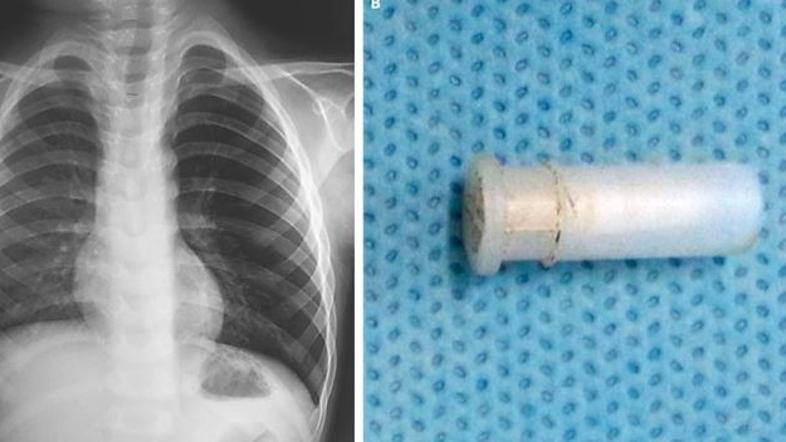

Fatiča so odpeljali na rentgen prsnega koša, kjer jih je čakalo presenečenje, pljuča so bila namreč napihnjena kot balon - preveč ujetega zraka v pljučih imenujemo hiperinflacija.

Zaskrbljeni zdravniki so takoj opravili bronhoskopijo in ugotovili, da se v dečkovih pljučih nahaja igrača - piščalka. "Tuja telesa v dihalnih poteh so pogost pojav, živžgajoči kašelj ob tem pa je izjemno redek,"  je za Live Science dejal Dr. Pirabu Sakthivela z Indijskega inštituta za medicinske vede.

Igračo, ki jo je štiriletnik pogoltnil dva dni prej, so mu odstranili in fant je danes zdrav.